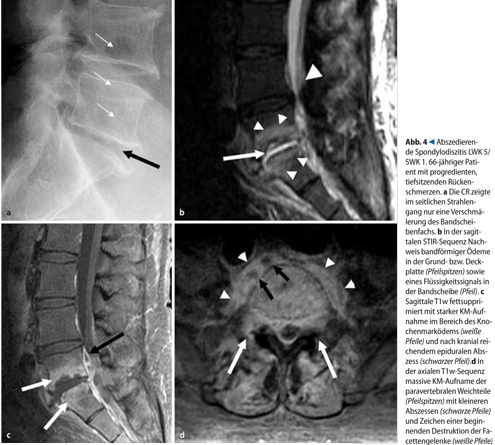

Röntgenologisches Frühzeichen derS pondylitis ist die Höhenminderung des Zwischenwirbelraums sowie im Verlauf zunehmende Unschärfe der Grund- und Deckplatten, die allerdings bereits einem fortgeschrittenen MRT-Stadium entspricht. Spätzeichen sind Spongiosklerose, Keilwirbelbildung mit Ausbildungeiner Kyphose sowie, bei chronischer Persistenz, ausgeprägte Sklerosesäumeum die Substanzdefekte. Mit der MDCT lassen sich destruktive Veränderungen erfassen, jedoch ist dieS pezifität bezüglich der Genese der Läsiongering. Die CT eignet sich jedoch hervorragend zur therapeutischen Abszessdrainage paravertebraler Abszesse sowiezur diagnostischen Wirbelkörperpunktion. Die Methode der Wahl zur Diagnosestellung einer Spondylitis bzw. Spondylodiszitis stellt die MRT-Untersuchungdar (s.Abb. 7). Mit dieser Modalität können zusätzlich paravertebrale sowie epidurale Abszesse in Lokalisation und Ausdehnung genau beurteilt werden (s.Abb. 4). Differenzialdiagnostisch machen das gleichzeitige Auftreten eines Diskusödems und fehlende degenerative Diskusveränderungen die Frühform der Spondylitis von der Degeneration (Modic1) unterscheidbar. Eine KM-Gabeist wegen der entzündlichen Aktivität und Ausdehnung erforderlich und kann zur Differenzierung zwischen Osteochondrose und Spondylodiszitis entscheidend beitragen.